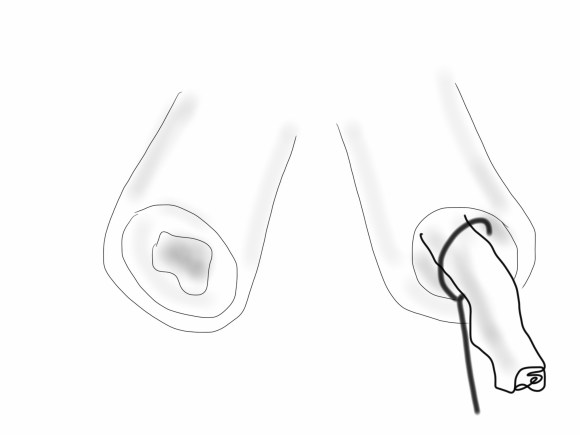

The common femoral endarterectomy rarely ends at the inguinal ligament, and is uniquely suitable for remote endarterectomy, a procedure from the early to mid twentieth century.

The addition of modern fluoroscopic imaging and combining with endovascular techniques makes this a safe and durable operation.

The common femoral endarterectomy is done from its distal most point and the Vollmer ring is used to mobilize the plaque. A Moll Ring Cutter (LeMaitre Vascular) is then used to cut the plaque.